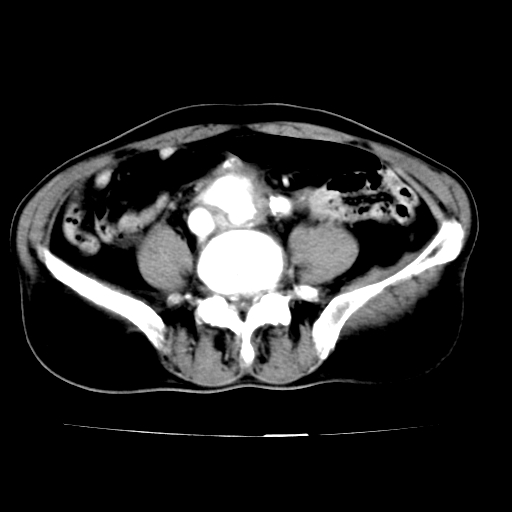

男,75岁,腹痛月余,彩超发现脐周腹主动脉异常回声。临床诊断:腹主动脉瘤。

ct诊断:右骼总动脉囊性动脉瘤并瘤内附壁血栓形成,与下腔静脉之间形成动静脉瘘。

请问各位老师:能排除动脉瘤破裂的可能吗?

各位老师注意到下腔静脉的充盈缺损了吗?注意到动静脉漏了吗?

当时是扫描的标准动脉期,可是下腔静脉与腹主动脉同步强化且幅度一致。所以我想动静脉瘘是存在的。